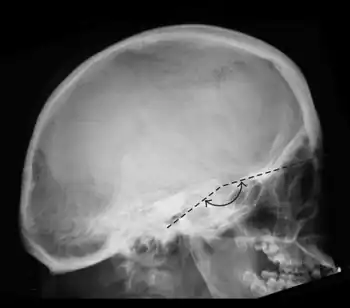

| Platybasia-a flat cranial base as a consequence of a flat nasion-sella-basion angle | |

| Symptoms | Platybasia is characterised by abnormal flattening of the skull base as defined as a base of skull angle over 143º.In the absence of neural compression, pain at the back of the skull and upper part of the neck is the most common symptom. Neural compression may affect the medulla and nerve roots from the lower brainstem, particularly those that might affect swallowing and the cough reflex. |